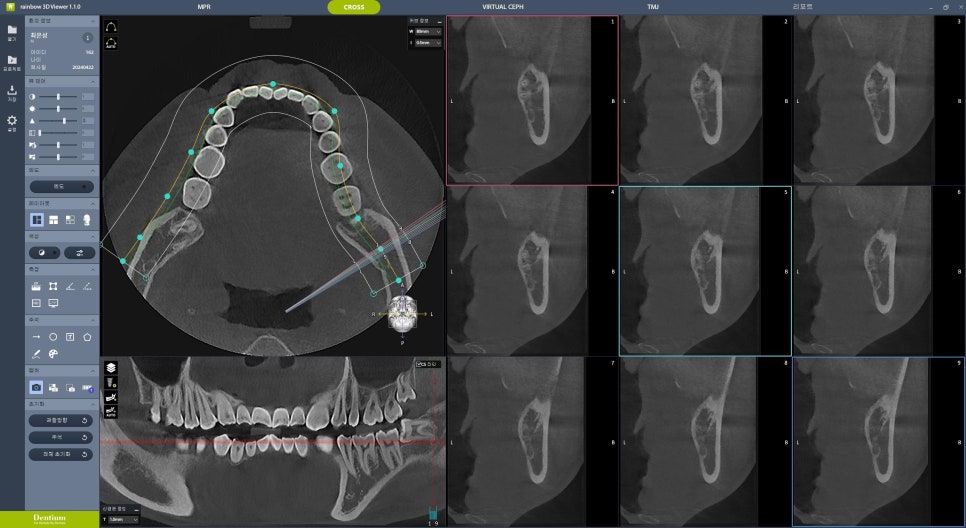

사랑니가 썩어있었기 때문에 뽑아야했지만,

사랑니 뿌리 끝과

중요한 하치조신경관이 가까워

CBCT를 찍어 분석했는데

다행히 문제가 없어 보여서

발치를 하기로 했었는데요